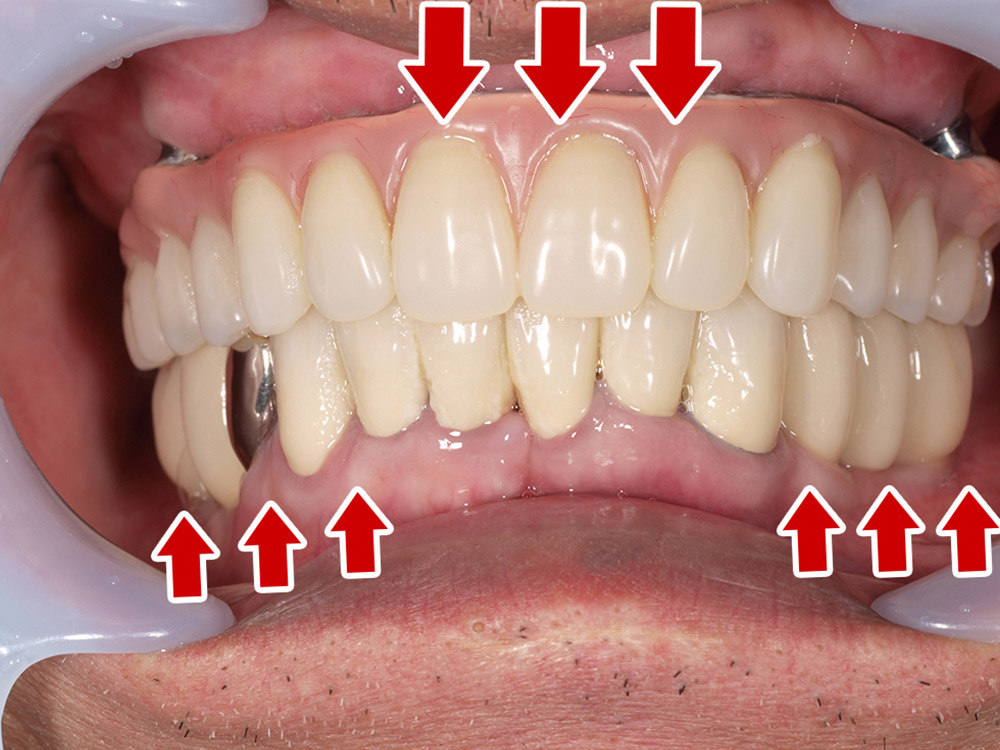

症例紹介

- 主訴

- 入れ歯が合わない。食べにくい。人生を豊かにしたい。

- 処置内容

- 上顎4本で12歯(オールオン4)、下顎4本5歯。

上下抜歯即時埋入、即時荷重(手術当日にインプラントの上に仮歯装着)

- 治療費用

- 上顎:約290万(税込)、下顎:約210万円(税込)

- 治療期間・通院回数

- 上顎:9か月/9回

下顎:6か月/7回

- リスク

- 術後の腫れ、痛み(ピークは3日後、1週間で軽減)

上部構造物、仮歯の破折、人工歯根脱落リスクがあります